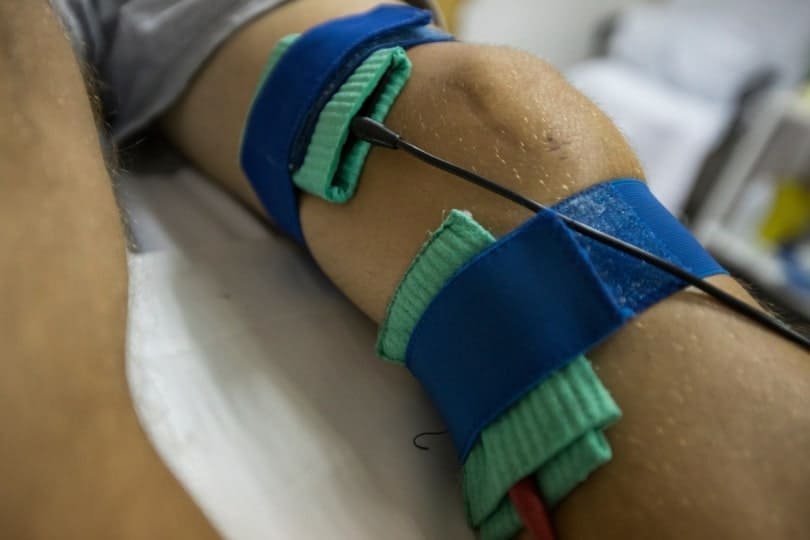

ACL - LIGAMEN PUTUS

Ligamen ACL yang tercedera akan terkoyak dan terputus seperti tali guni dan tidak dapat sembuh dengan sendiri.

Tanpa ACL, lutut akan mudah terkehel atau terpelecok dengan sendiri dan anda mungkin akan terjatuh secara tiba-tiba disebabkan ketidakstabilan sendi lutut.

Tanpa ligamen ini aktiviti harian biasa yang tidak lasak seperti berjalan dan menaiki tangga atau sembahyang masih boleh dilakukan.